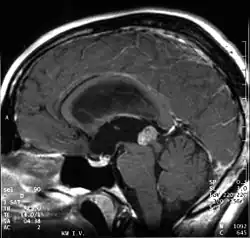

Papillary tumors of the pineal region were first described by A. Jouvet et al. in 2003[1] and were introduced in the World Health Organization (WHO) classification of central nervous system in 2007.[2] Papillary Tumors of the Pineal Region are located on the pineal gland which is located in the center of the brain. The pineal gland is located on roof of the diencephalon. It is a cone-shaped structure dorsal to the midbrain tectum.[3] The tumor appears to be derived from the specialized ependymal cells of the subcommissural organ.[1][4][5] Papillary tumors of the central nervous system and particularly of the pineal region are very rare and so diagnosing them is extremely difficult.[6]

Papillary tumors of the pineal region are normally well circumscribed. They are reported to be fairly large ranging between 2.5 and 4.0 centimeters. These tumors sometimes feature a cystic component.[13]